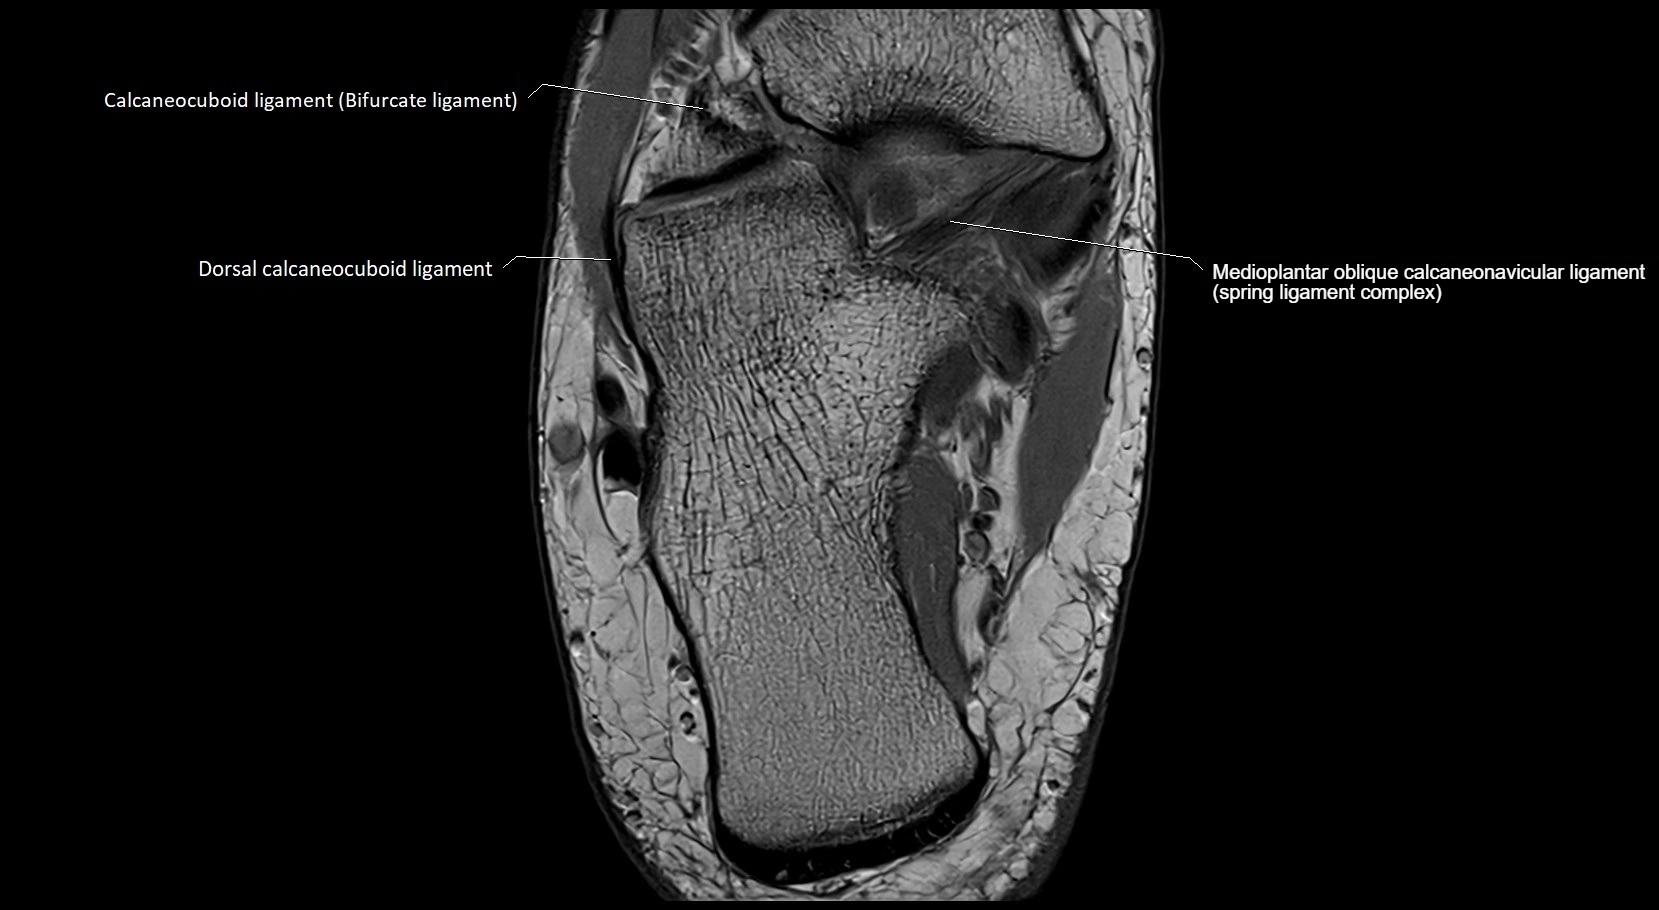

MRI image

image